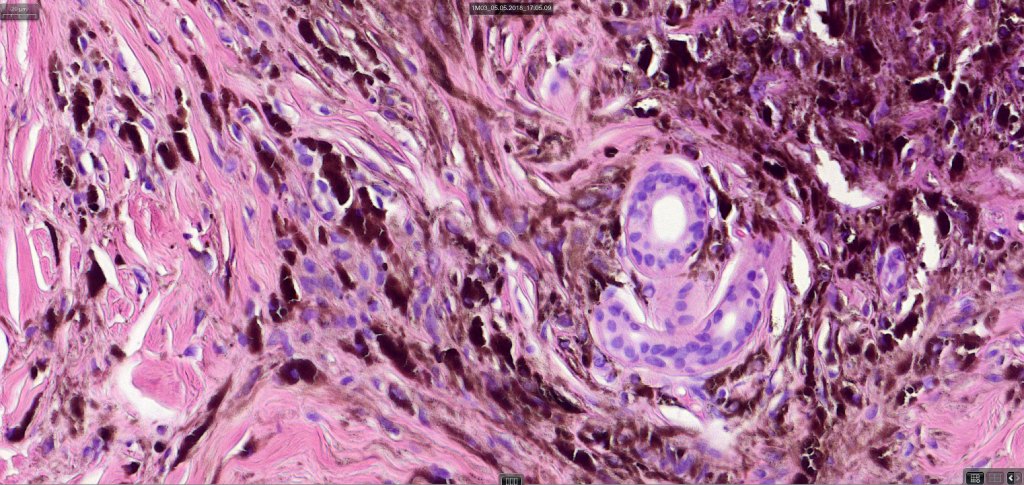

•Most characteristic is the dumbbell silhouette although a plague morphology may also be encountered

•Admixture of spindle cells, pigmented bipolar or dendritic cells & melanophages

•Cytoplasm is pale and nuclei are small with inconspicuous nucleoli

•An alveolar pattern is characteristic particularly with clear cell nodules

•Multinucleate giant cells sometimes present

•Stromal fibrosis, myxoid change, vascular hyalinization with cyst formation are often seen